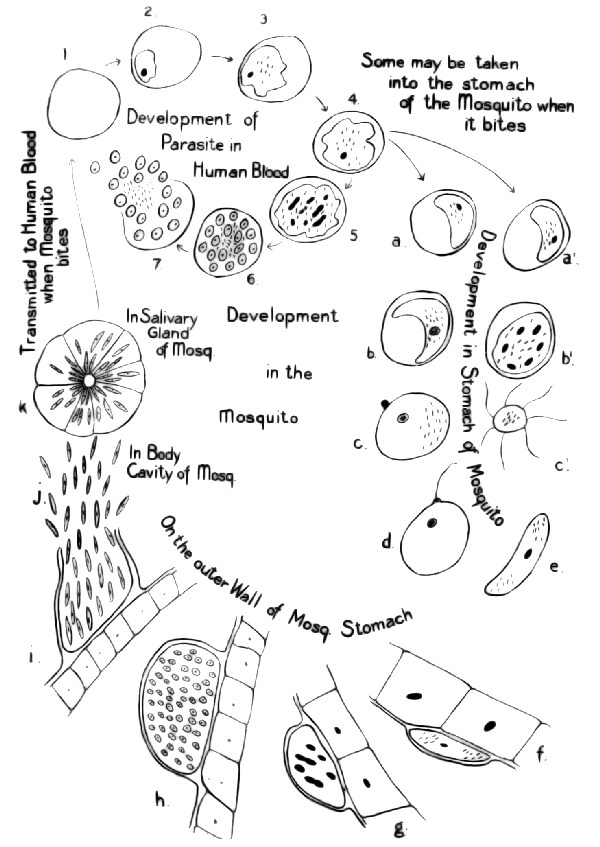

| Fig. 99. | Diagram to illustrate the life-history of the malarial parasite | 110 |

Early reference to malaria, 106; its general distribution, 106; theories in regard to its cause, 107; insects early suspected, 107; The parasite that causes malaria, 108; studies of the parasite, 108; Life-history in human host, 109; its effect on the host, 110; the search for the sexual generation, 111; The parasite in the mosquito, 112; review of whole life-history, 115; malaria transmitted only by mosquitoes, 115; Summary, 117; experimental proof, 118. |